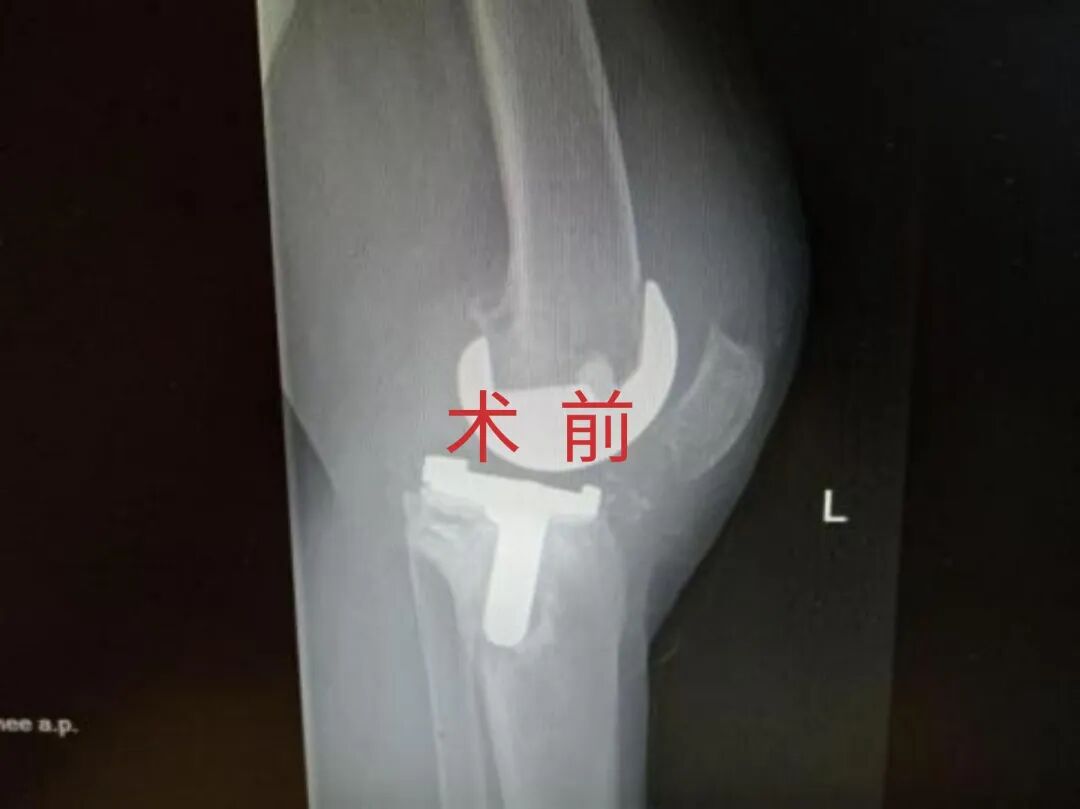

多年来,贵州航天医院各科室紧跟医学前沿,不断强技术、补短板,大力开展新技术、新项目,完成了许多高精尖、高难度、本地区“首例”的技术,填补了医院医疗技术空白,满足了群众日益增长的医疗需求。 贵州航天医院骨科率先在遵义地区开展骨搬移技术,截至目前,已治愈慢性骨髓炎、感染性骨不连、骨缺损、脉管炎、糖尿病足患者200余例,糖尿病足治疗保肢率达到98%。 本期,我们将为大家带来骨科特色技术——骨搬移技术(Ilizarov)。 案例分享 一名59岁的患者,身患糖尿病12年,在来我院3个月前出现了右脚溃烂的症状,来院就诊时,患者的右脚十分红肿,右脚脚趾坏死,伤口处不断流出黑红色脓液,情况十分严重。在接诊到患者时,骨科专家团队高度重视,立刻为患者完善了CT血管造影(CTA)等相关检查,诊断为:2型糖尿病,糖尿病周围血管病变,右糖尿病足。 术 前 考虑到患者情况比较严重,为最大限度保证患者肢体完整,科室专家团队进行了严格的讨论评估,为患者制定了骨搬移技术治疗方案,在征得患者及其家属的同意后,成功通过搬移骨块为患者进行治疗,促进患者病变肢体血管再生。 胫骨横向骨搬移外架固定 清除感染病灶 术后调节外架,通过搬移骨块 促进患肢血管再生 患者在术后三周前来换药,观察到感染得到进一步控制;术后六周复查,患者病变处已愈合,进行CT血管造影(CTA)后可明显观察到足部血管再生。 术后3周 术后6周愈合 CT血管造影见足部血管再生 糖尿病患者全身与局部的问题互为影响,形成恶性循环,糖尿病足溃疡创面迁延不愈,常见干性坏疽、湿性坏疽、趾坏死、深且大的溃疡以及骨髓炎等症状,还可导致脓毒血症,以往为保全生命,患者被迫选择一次或多次截肢。骨搬移技术的发展进步,能在血糖有效控制、局部有效清创下,有效促进患肢微血管再生,改善患肢血供,达到糖尿病足更快治疗康复的目的,并能根据病变情况最大限度的保障患者肢体完整。 什么是骨搬移技术 骨搬移技术是通过使用专用的骨外固定器固定骨段,每天缓慢牵拉,在牵拉搬移过程中,骨段尾部形成新骨及新的软组织,从而修复骨骼缺损及软组织缺损。是治疗大段骨缺损、骨不连、骨感染、肢体畸形的金标准方法,也用于治疗脉管炎、糖尿病足等肢体缺血性疾病。 骨感染缺损 切除感染段 搬移骨段 新骨形成 骨感染根治愈合 骨搬移技术原理 生物组织在持续、稳定、缓慢牵拉下,能刺激细胞分裂、组织再生,骨外固定技术运用该原理,通过持续缓慢调节外固定器形成牵拉张力,促进牵引成骨与相邻组织再生,如神经、血管、肌肉、皮肤等再生,达到治疗大段骨缺损、肢体缺血如糖尿病足等疾病的目的。 骨搬移技术优势 (一)除治疗骨缺损、骨不连外,有更广的适用范围,利用组织再生、血管再生等特性,能大量运用于肢体畸形的矫形、糖尿病足等的治疗。 (二)治疗效果确切,重建肢体外型和功能,极大降低截肢率和残疾率。 (三)明显提高了患者生活质量,极大减轻其家庭及社会负担。 肢体畸形的矫形 慢性骨髓炎 骨段切除 术后1年 濒临截肢的脉管炎术后6周 难愈创面术后3周 贵州航天医院骨科 专家团队 赵学平 骨科主任 主任医师 临床擅长:从事骨科临床工作30余年,对骨科常见疾病的诊治具有丰富的临床经验。 世界中医药联合会脊柱康复专业委员会常务理事,中华中医药学会整脊分会常务委员,中国中西医结合学会骨伤科分会肢体矫形功能重建与康复专家委员会常务委员,中国研究性医院学会骨科创新与转换专业委员会关节外科学组保髋工作委员会常委,中国康复技术转化及发展促进会骨外科与康复技术转化专业委员会常务委员,泛珠三角区域运动医学联盟(PPRD-SMA)理事会常务理事,中国研究型医院学会运动医学专业委员会委员,贵州省中医药学会整脊分会副主任委员,贵州省中西医结合学会银质针专业委员会副主任委员,贵州省康复医学会骨与关节专业委员会常务委员,贵州省人民医院骨科专科联盟常务理事,贵州省康复医学会骨内科专业委员会常务委员,中华医学会贵州省骨科学会委员,贵州省康复医学会脊柱脊髓专业委员会常务委员,贵州省运动医学分会委员,贵州省康复医学会骨与软组织肿瘤专业委员会委员,遵义市医学会创伤分会副主任委员,贵州省康复医学会骨内科专业委员会遵义地区分会常务委员,遵义市医疗事故鉴定、伤残鉴定、工伤鉴定、司法鉴定专家。 长期从事骨科临床研究及教学工作,在国家级、省部级杂志发表论文20余篇,SCI论文2篇,参与主编骨科专著2部,主持省部级科研项目2项,参与指导省部级、市级科研项目6项。 陈明勇 骨科副主任 副主任医师 临床擅长:从事创伤骨科工作约20年,对骨缺损、骨不连、骨肿瘤、肢体畸形等的肢体矫形重建及功能重建,慢性化脓性骨髓炎的根治治疗、糖尿病足的保肢治疗、快速康复理念(ERAS)下的老年骨折的诊治,四肢复杂骨折的诊治,四肢骨折等微创手术治疗具有丰富的临床经验。 2004年毕业于遵义医学院临床专业,曾在中国人民解放军总医院、广西医科大学第一附属医院、上海第六人民医院骨科进修。中国中西医结合学会骨伤科专业委员会横向骨搬移治疗糖尿病足及微血管网再生学组首届委员,遵义市医学会创伤分会常务委员。 瞿 辉 骨科 副主任医师 临床擅长:对骨科的常见病、关节外科、脊柱外科及运动医学疾病的诊治具有丰富的临床经验,熟练掌握骨科手术操作技术。 毕业于遵义医学院临床医学系,2005年前往广州中山大学第一附院骨显微医学部进修学习,2011年前往成都华西医院进修学习,并多次在省内外学习骨科相关知识,是中华医学会骨科分会会员。 赵兴东 骨科 主任医师 临床擅长:擅长骨科的常见病及各种创伤、四肢骨折创伤修复、骨感染、手足疾病的诊治和手足体表畸形的矫形整复,熟练掌握骨科四肢骨病及创伤的手术操作技术,尤其在四肢关节复杂性损伤、手足外伤、组织缺损创面、难治创面的皮瓣修复方面及平足、高弓足矫形方面及四肢慢性疼痛诊治、康复方面具有丰富的临床经验。 硕士研究生,毕业于遵义医学院临床外科系,2015年前往山东省立医院手足外科进修学习;遵义市医学分会创伤分会第一、二届委员,遵义市手外科医学会第二委届员会常务委员;在省级及省级以上期刊发表文章9篇,参编著作2部,参与主持并完成市级课题1项,参与市级课题2项、省级课题1项。 张俊凯 骨科 副主任医师 临床擅长:从事骨科临床工作28年,对创伤骨折、骨感染、骨缺损、骨不连等外科诊治,四肢骨折的微创手术治疗,四肢复杂骨折(如关节内粉碎性骨折、多发骨折等)的损伤控制及手术治疗等具有丰富的临床经验。 1995年毕业于遵义医学院临床专业,2009年前往复旦大学附属医院骨科进修1年。 卢懿明 骨科 副主任医师 临床擅长:从事骨科工作18年,对创伤骨折、四肢骨折的微创手术治疗、四肢复杂骨折(如关节内粉碎性骨折、多发骨折等)的损伤控制及手术治疗,尤其是髋部骨折的PFNA等微创技术,踝关节骨折、膝关节周围骨折的Mipo微创技术等具有丰富的临床经验,开展了4项新技术,发明6项新型专利技术。 2005年毕业于遵义医学院临床专业,2017年,前往南方医科大学第三附属医院骨科进修半年,回院后运用Mipo技术对骨干骨折及干骺端骨折的治疗技术,同时积极开展骨盆骨折、髋臼骨折腹直肌外侧切口的应用;发表了多篇专业论文,经常参与省内外学术交流会授课,获得医院荣誉称号多个。 邬夏荣 骨科 副主任医师 临床擅长:从事骨科工作16年,对四肢复杂骨折、骨肿瘤的诊治,尤其是足踝创伤、慢性踝关节损伤、平足症等诊疗具有丰富的临床经验。 2006年毕业于遵义医科大学临床医学专业,曾在陆军军医大学西南医院进修学习,发表多篇骨科学术论文。 余德怀 骨科 副主任医师 临床擅长:从事骨科工作10余年,对运动医学、骨关节、脊柱外科常见病、多发病的诊治具有丰富的临床经验。 硕士研究生,2011年毕业于遵义医学院临床医学专业,曾前往遵义医科大学附属医院运动医学专业进修学习;是贵州省医学会运动医学分会青年委员,西部关节镜联盟委员;发表多篇骨科学术论文。 冯 乾 骨科 副主任医师 临床擅长:从事骨科工作近20年,熟练掌握骨科多发病及常见病的诊治,尤其对脊柱退变性疾病的诊断及治疗具有丰富的临床经验,主要研究脊柱微创相关治疗方式,能熟练开展椎间孔镜及VBE。 曾前往北京大学第三医院进修学习疼痛及椎间孔镜、首都医科大学友谊医院专业进修脊柱内镜;是贵州省康复医学会第三届脊柱脊髓专业委员会委员;发明专利3项、发表脊柱外科专业论文多篇。 张艳金 骨科 副主任医师 临床擅长:从事骨外科工作16年,对复合伤、多发伤的救治、四肢骨干骨折、关节周围骨折、骨肿瘤、骨髓炎等诊治具有丰富的临床经验。 中共党员,硕士研究生,2006年本科毕业于山西医科大学第二临床医学院,2011年研究生毕业于北京军区总医院;在“老年COPD患者合并髋部骨折的诊治”国际合作课题组研究两年,在老年髋部骨折的诊治方面具有丰富的经验,并发表论文6篇;承担遵义市级课题1项;承担遵义医科大学的临床教学工作,获得遵义医科大学优秀带教老师荣誉。编撰有《骨科疾病诊疗精粹》一书,开展2项新技术,编撰地方规范《务川自治县创伤骨科常见疾病诊疗规范》一书。 赵小锋 骨科 副主任医师 临床擅长:从事骨科临床工作11年,对骨科常见病、多发病诊疗有较为丰富的临床经验,擅长脊柱相关疾病诊断及治疗,尤其是颈、腰、腿疼痛疾病诊断及治疗,擅长胸腰椎骨折微创经皮穿刺内固定术、经皮穿刺椎体成形术、经皮穿刺脊柱内镜下腰椎间盘摘除术、单纯开创腰椎间盘摘除术、腰椎滑脱复位椎间植骨椎融合内固定术、腰椎管狭窄减压融合内固定术及人工髋、膝关节置换术等。 2012年毕业于遵义医学院外科学专业硕士研究生,2019年参加“遵义市115医学人才精英计划”于上海交通大学第一附属医院培训学习,2023年于北京大学第三人民医院脊柱外科进修学习,曾获得遵义市优秀医师荣誉称号。 遵义市手外科第一届委员,遵义市医学会创伤分会第一届委员,遵义市医学会创伤分会第二届委员,贵州省康复医学会第三届脊柱脊髓专业会委员,遵义市医学会烧伤与整形外科学分会委员,发表论文5篇,其中国家级核心期刊1篇,SCI论文1篇,主持市级课题1项并结题,参与市级课题2项。 贵州航天医院骨科简介 基本情况 贵州航天医院(原3417医院)骨科组建于1968年,前身是以创伤和断肢(断指)再植闻名于世的上海市第六人民医院骨科,中国断肢(断指)再植的奠基者、中科院院士陈仲伟等著名专家、学者多次莅临科室指导医疗、教,是贵州省最早拥有专业骨科技术科室之一,在70年代开展了贵州省首例断肢(断指)再植手术。组建50余年来,诊治患者已逾百万,挽救了无数的伤病员,成为了保障遵义地区人民群众健康的重要支撑。 经过几代人的不懈努力,今天的骨科,已由创伤骨科发展至骨病、骨肿瘤、骨结核等领域,现有脊柱外科、关节外科、四肢创伤、手足外科四个亚专科,成为了集医疗、教学、科研于一体的综合学科,是贵州省临床重点专科、遵义市临床重点专科、遵义市骨科临床医学中心、遵义市基层骨科专科联盟理事长单位。 科室目前开放床位110张,共有医护人员50余人,副高级以上专家18人,硕士研究生15人。拥有一流骨科医疗设备多台,每年不定期选派优秀技术骨干到全国各大知名医学院校进修、学习、参观、交流,并邀请国内、国外知名专家教授来院进行交流、指导,通过不断引进国内外先进的诊疗技术,科室医疗技术水平稳步提升,为广大人民群众提供了优质的医疗服务。 专科特色 骨一科 (一)骨缺损、骨不连的肢体与功能重建 胫骨横向骨搬移技术治疗糖尿病足: (二)慢性骨髓炎的根治治疗 (三)肢体缺血性疾病如糖尿病足、脉管炎的保肢治疗 (四)皮瓣修复 (五)复杂创伤的治疗 (六)老年髋部骨折及小儿骨折快速手术 老年髋部骨折: 骨二科 (一)胸腰椎骨折微创经皮椎弓根螺钉固定术 (二)老年性骨质疏松性患者腰椎滑脱脊柱内固定术(骨水泥螺钉) (三)V形双通道脊柱内镜技术(VBE)腰椎融合术治疗腰椎退行性疾病 (四)老年性骨质疏松性骨折(PVP/PKP)术 (五)人工髋关节置换术 (六)双侧股骨头坏死人工全髋关节置换 (七)右侧全髋置换术后假体周围骨折翻修 (八)人工膝关节置换术 (九)人工膝关节假体松动翻修 (十)关节镜技术 传统手术切口 关节镜技术切口 诊疗范围 骨一科 1.四肢创伤、矫形。 2.手、足踝外科。 骨二科